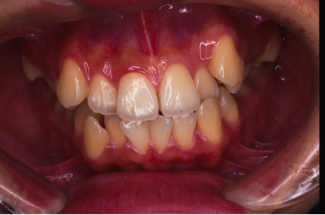

治療前

治療後

深い噛み合せを改善する治療が必要になりました。

先に深い噛み合せを上げないと矯正装置がつかないので、噛み合せの深さを改善する治療から行なう矯正治療となりました。